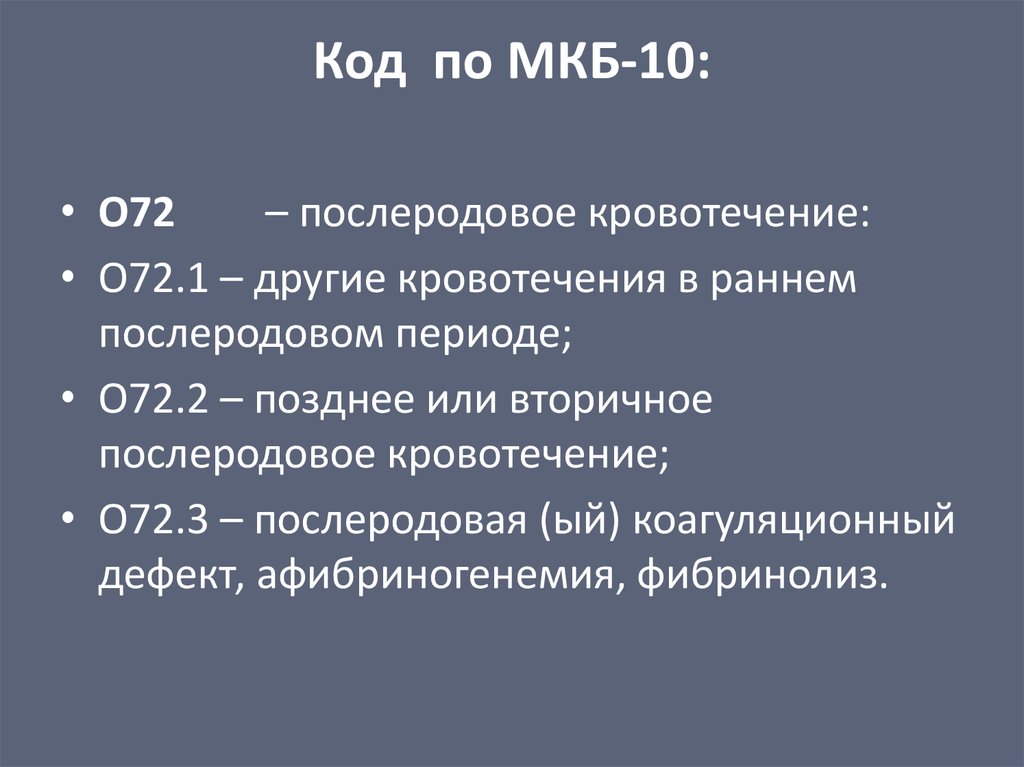

Код мкб 10 атерома головы

Код мкб 10 атерома головы 109 фото